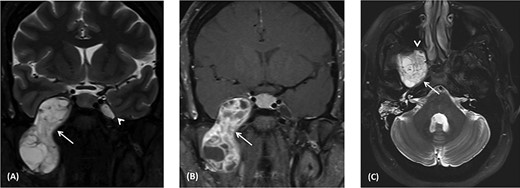

(A) Endoscopic view of the final surgical cavity after tumor removal. (B) Image-guided tumor removal from cavernous carotid artery.

The patient underwent an image-guided endonasal endoscopic tumor removal starting by endoscopic medial and posterior walls maxillectomies to control the tumor removal from the lateral sphenoid sinus and the infratemporal fossa after cauterization of the maxillary artery and sphenopalatine artery branches feeding the tumor. The tumor was dissected and removed from the cavernous (Fig. 3A) and petrous carotid artery in the middle cranial fossa (Fig. 3B). The middle cranial fossa’s dura was intact during the tumor removal (Fig. 3C). All the steps of tumor removal were controlled and monitored under image-guided navigation for accurate localization of tumor removal and avoidance of violation to the middle cranial fossa’s dura, or the brain, and the internal carotid artery in its cavernous and petrous segments (Fig. 4a and b).